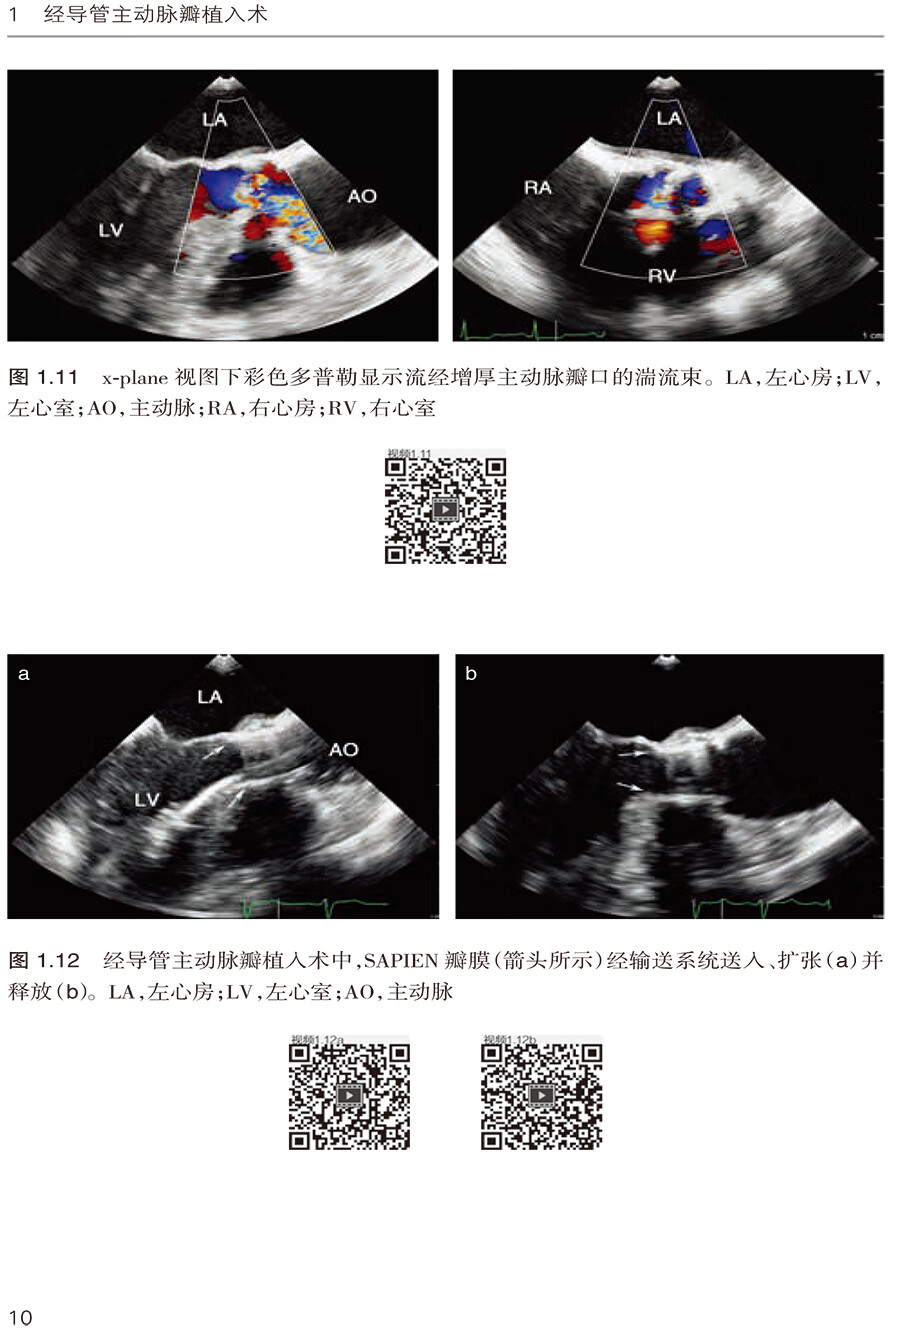

1.3 下肢动脉粥样硬化的经心尖SAPIEN 瓣膜植入术 /9